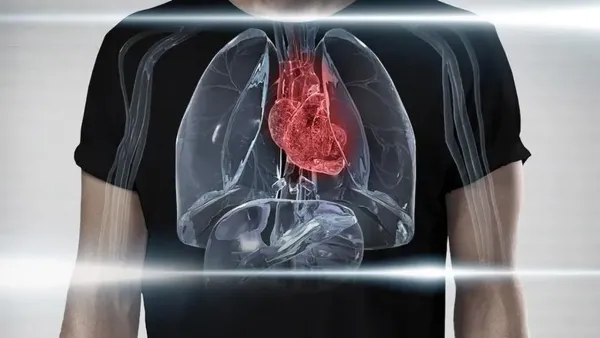

تحذير طبي عاجل.. 5 أسباب وراء التوقف المفاجئ لعضلة القلب وطرق الحماية منها

التوقف المفاجئ لعضلة القلب يعد من أكثر الهواجس الصحية إثارة للقلق في الآونة الأخيرة بعد رصد حالات متكررة بين فئات عمرية متباينة؛ مما دفع المؤسسات الطبية إلى ...